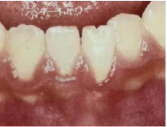

他のお友達は、「あ、歯ぐきがめくれてる!!」

歯でなく、歯ぐきを強く打ったようで、幸い歯にはダメージはなかったのですが、歯ぐきが切れて、ピロピロしてしまっていました(;´∀`)

乳歯のケガの場合、永久歯に生え変わると、歯ぐきがリニューアルされて元に戻りやすいのですが、永久歯のケガの場合、歯ぐきが下がったまま、なんてことになりかねません。

左の前歯に比べて、右の前歯の歯ぐきが下がっています。

歯ぐきを元の場所に戻して、縫ったり、口の中用の粘着剤を貼ったりする必要があります。